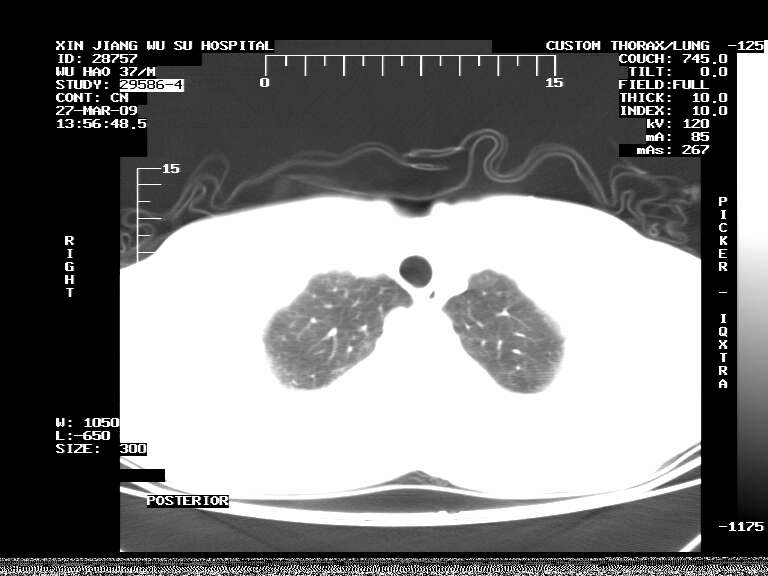

标题: CT19113:体检胸透发现阴影,CT图像。

男,37岁,体检胸透发现阴影。

患者体检发现 无症状 左肺下叶占位,边缘模糊,可见血管聚束、分叶、胸膜牵拉,增强呈不均匀性强化。 首先考虑左肺下叶周围型肺癌,建议穿刺活检。

患者体检发现 无症状 左肺下叶占位,边缘模糊,可见血管聚束、分叶、胸膜牵拉,增强呈不均匀性强化。 首先考虑左肺下叶周围型肺癌,建议穿刺活检。支持!

左肺下叶见一结节病变,边缘欠清不光滑,与胸膜粘连且胸膜局限性增厚,注药后呈环形强化,动脉期壁呈明显点环状强化,静脉期壁强化减低,中心密度低无强化,灶周无明显的卫星灶和水肿区(晕征)---考虑周围性肺癌,不除外感染性病变,建议穿刺活检。

左肺下叶软组织病灶,密度较高,内见点状钙化,其周围见子灶,邻近胸膜扁平样增厚.c+病灶强化明显,中心强化弱.诊断:左肺下叶结核瘤.

周围有卫星灶,胸膜反应不明显,病灶中心有坏死。建议先抗结核治疗后,短期复查

左肺下叶大片实变影,内靠胸膜见不规则更高密度结节灶,边缘强化,相邻胸膜增厚,胸膜下脂肪线存在。考虑炎症,结核可能。